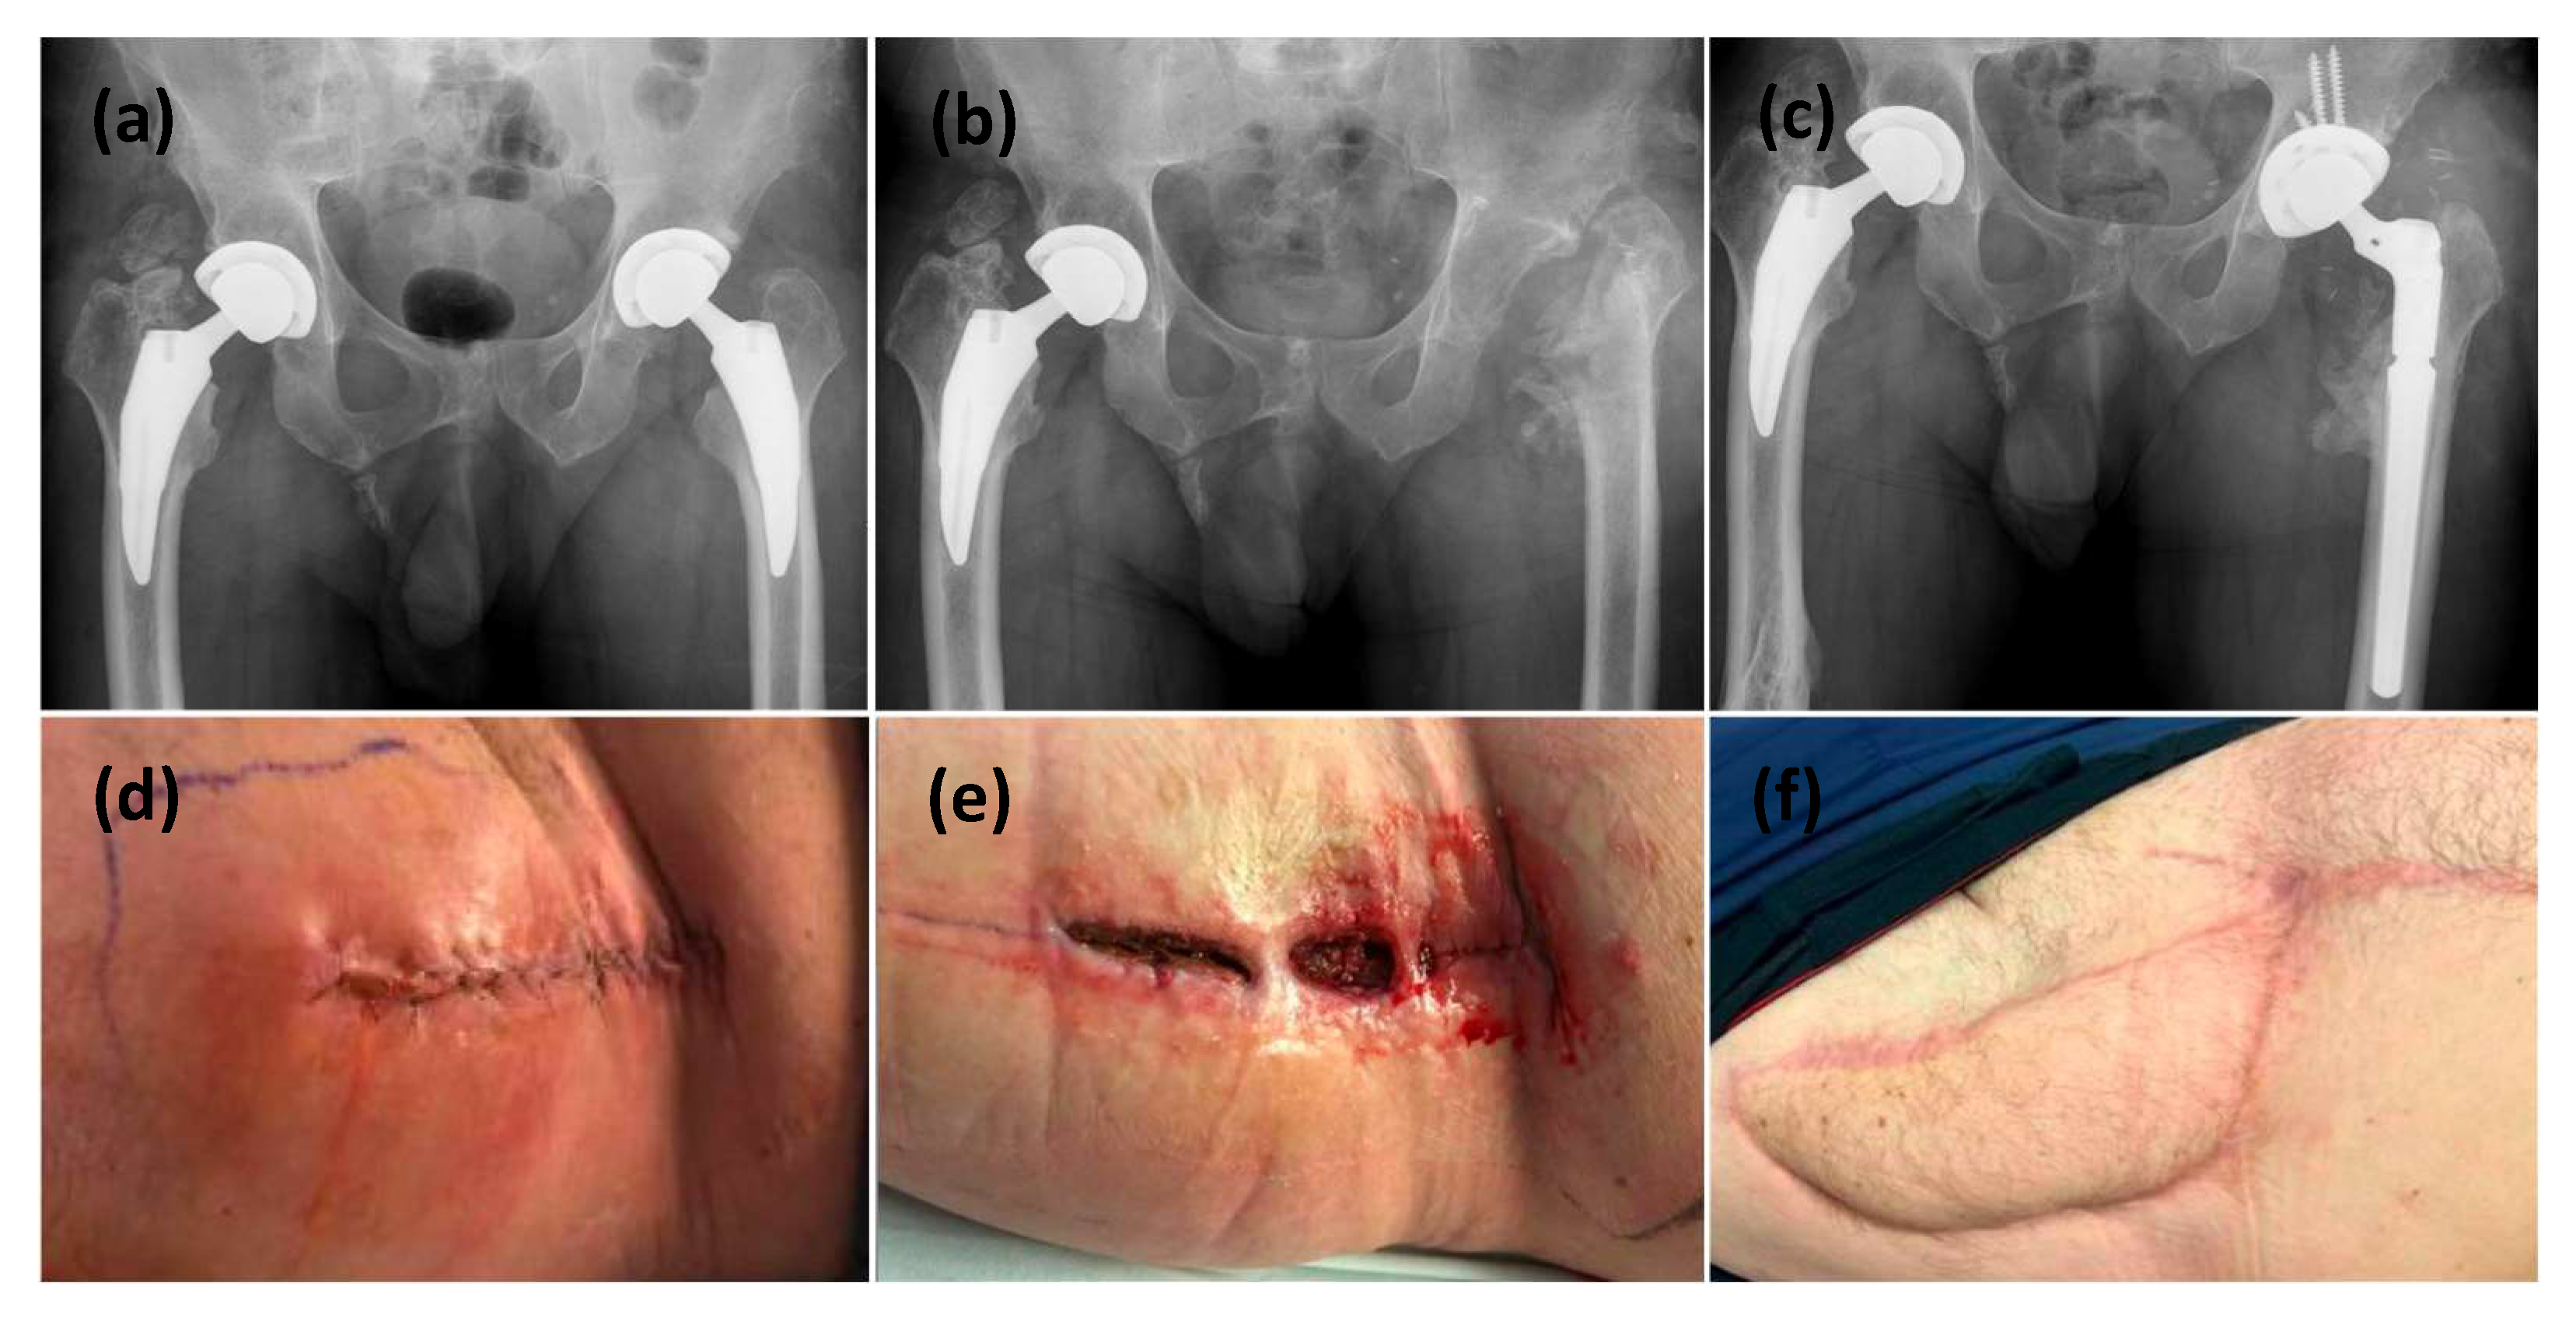

3.2. Surgical Outcomes, Complications, and Functional Outcome

| Patient | Surgical Approach | PJI Surgeries Before VRAM | PJI Surgeries After VRAM | Prior Flap Recon | Implant During VRAM |

|---|---|---|---|---|---|

| 1 | Posterior | 2 | 0 | No | Retained |

| 2 | Posterior | 5 | 0 | GM | Retained |

| 3 | Anterior | 3 | 5 | GM | Retained |

| 4 | Posterior | 8 | 0 | TFL | Removed |

| 5 | Anterior | 3 | 0 | No | Removed |

| Patient | Follow Up Duration | Complication | Clavien-Dindo Classification | Flap Condition | Wound Condition | Chronic Suppression | Implant | Function |

|---|---|---|---|---|---|---|---|---|

| 1 | 24 M | Graft edge necrosis, Donor site dehiscence, Ventral hernia, seroma | II, IIIa | Viable | Draining sinus | none | Retained | Ambulating with walker |

| 2 | 12 M | Ventral hernia | I | Viable | Healed | Abx | Retained | Ambulating with walker |

| 3 | 47 M | Graft edge necrosis, Donor site dehiscence | II | Viable | Healed | none | Retained | Ambulating with walker |

| 4 | 40 M | Donor site dehiscence. | II, IIIa | Viable | Healed | Abx | Retained | Ambulating with walker |

| 5 | 17 M | Graft site dehiscence | II | Viable | Healed | Abx | Retained | Independent ambulation |